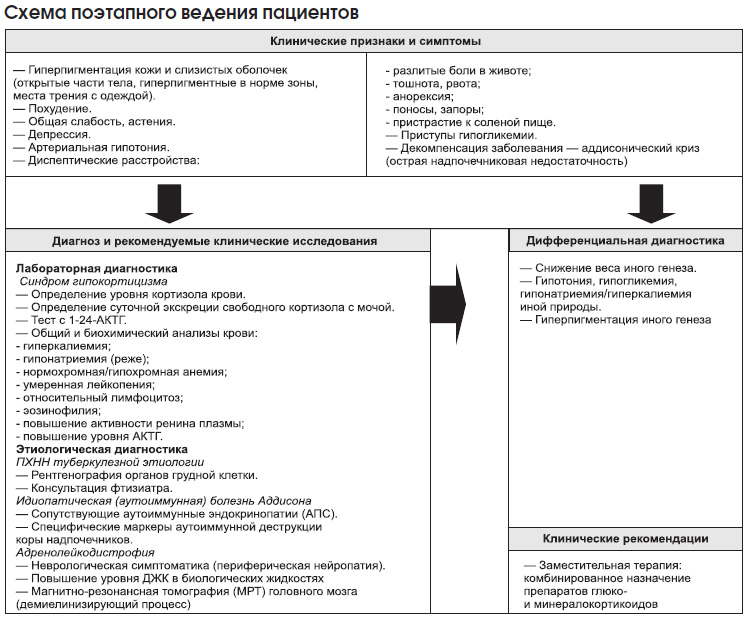

Клинические признаки и симптомы

— Гиперпигментация кожи и слизистых оболочек.

— Похудение.

— Общая слабость, астения, депрессия.

— Артериальная гипотония.

— Диспептические расстройства (разлитые боли в животе, тошнота, рвота, анорексия, поносы, запоры).

— Пристрастие к соленой пище.

— Приступы гипогликемии.

Диагноз и рекомендуемые клинические исследования

Диагностический поиск при ПХНН включает следующие этапы:

— оценка клинических проявлений (на основании данных клинической картины высказывается предположение о наличии ПХНН);

— лабораторное подтверждение синдрома гипокортицизма (на этом этапе при помощи гормональных исследований, объем которых определяется конкретной клинической ситуацией, необходимо доказать или отвергнуть наличие дефицита кортикостероидов);

— этиологическая диагностика (выяснение причины деструкции коры надпочечника).

Лабораторное подтверждение синдрома гипокортицизма

Определение уровня кортизола крови имеет ограниченное диагностическое значение, поскольку у многих больных ПХНН он нередко оказывается на нижней границе нормы.

Простым, но недостаточно надежным методом диагностики ПХНН является определение суточной экскреции свободного кортизола с мочой. При развернутой клинической картине первичного гипокортицизма обнаружение значительного снижения суточной экскреции свободного кортизола с мочой позволяет подтвердить диагноз и приступить к лечению.

При стертой клинической картине ПХНН, а также при пограничных или сомнительных результатах определения экскреции кортизола пациентам показано проведение теста с 1-24-АКТГ (первые 24 аминокислоты 39-аминокислотной молекулы АКТГ). Проведение теста с 1-24-АКТГ целесообразно в любой ситуации, когда врач не имеет опыта работы с больными ПХНН или у пациента отсутствует хотя бы один из таких симптомов, как выраженная меланодермия, похудение, артериальная гипотония и диспепсия. Стимуляционный тест с исследованием уровня кортизола плазмы через 30 и 60 мин после внутривенного введения 250 мг (25 ЕД) 1-24-АКТГ на 5 мл физиологического раствора — классическое исследование в диагностике первичного гипокортицизма. Повышение уровня кортизола более 500 нмоль/л надежно исключает ПХНН.

Результаты общего клинического и биохимического анализов крови имеют ограниченное значение в диагностике ПХНН. Для ПХНН характерны гиперкалиемия и, реже, гипонатриемия, нормохромная или гипохромная анемия, умеренная лейкопения, относительный лимфоцитоз и эозинофилия. Кроме того, при ПХНН отмечают повышение активности ренина плазмы и уровня АКТГ.

Этиологическая диагностика

— Исключение туберкулезной этиологии ПХНН (рентгенография органов грудной клетки, консультация фтизиатра).

— При отсутствии данных о туберкулезном процессе устанавливают диагноз предположительно идиопатической (аутоиммунной) болезни Аддисона. Веским аргументом в пользу этого диагноза служит наличие у пациента сопутствующих аутоиммунных эндокринопатий, т.е. АПС. Специфическими иммунологическими маркерами аутоиммунной деструкции коры надпочечников являются аутоантитела к ферментам надпочечникового стероидогенеза — 21-гидроксилазе (Р450с21), 17-гидроксилазе (Р450с17) и ферменту отщепления боковой цепи (P450scc). При изолированной ПХНН наибольшее диагностическое значение имеют антитела к Р450с21. Метод применяется редко.

— АЛД можно заподозрить при сочетании ПХНН с различного рода неврологической симптоматикой (в частности, с периферической нейропатией). Лабораторным маркером АЛД является повышение уровня длинноцепочечных жирных кислот в биологических жидкостях. Определяют уровни тетракозановой (С24:0), пентакозановой (С25:0) и гексакозановой (С26:0) кислот в плазме, а также их отношение к уровню бегеновой кислоты (С22:0). При подозрении на АЛД обязательным исследованием является МРТ головного мозга для выявления демиелинизирующего процесса.

Дифференциальная диагностика

Дифференциальную диагностику ПХНН проводят со следующими заболеваниями и состояниями:

— снижение веса иного генеза;

— гипотония, гипогликемия, гипонатриемия/гиперкалиемия иной природы;

— гиперпигментация иного генеза.

Клинические рекомендации

Заместительная терапия ПХНН подразумевает обязательное комбинированное назначение ГКС и минералокортикоидов.